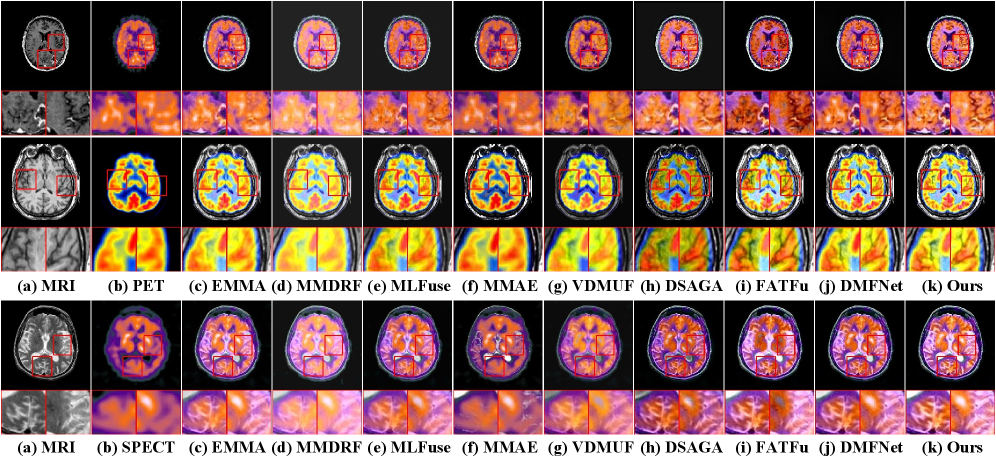

MRI functional image fusion (Figure 7) requires highlighting metabolic hotspots while preserving anatomical context. EMMA, MMDRFuse, and MMAE allow functional information to obscure anatomical details. VDMUFusion weakens metabolic information and causes severe texture loss. DSAGAN’s aggressive contrast enhancement introduces background artifacts. FATFusion preserves MRI structure but completely loses the high-intensity metabolic regions from the functional image. MLFuse also weakens some details. In contrast, our method and DM-FNet effectively integrate the functional tracer’s intensity and distribution into the precise MRI anatomical background, which is more conducive to accurate clinical diagnosis.

Refer to caption

Figure 7: Visual comparison with eight SOTA methods in MRI-PET and MRI-SPECT.